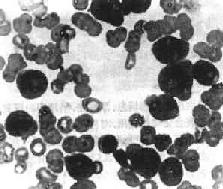

| 一、急性白血病急性白血病起病急,常表现为发热、乏力、进行性贫血、出血倾向、淋巴结及肝、脾肿大等。 急性白血病时造血干细胞或原始和幼稚的白细胞恶变,发生分化障碍,不能分化为成熟的细胞,使骨髓内原始和幼稚细胞大量堆积,成熟的细胞明显减少。大量异常的原始和幼稚幼胞增生,抑制正常的造血干细胞和血细胞生成,引起红细胞、白细胞和血小板减少。多能造血干细胞分化过程中的任何阶段都可能发生恶变转化为白血病细胞。根据累及的细胞类型可分为急性淋巴细胞性白血病(ALL)和急性粒细胞性白血病(AML)。 (一)急性淋巴细胞性白血病 本病多见于儿童和青年人。根据形态学和免疫学特点可分为不同的亚型。 1.国际上通用的法、美、英协作组的FAB分类,根据瘤细胞形态将急性淋巴细胞性白血病分为L1,L2,和L3型。 L1型:细胞较小,大小一致。核较大,圆形,染色质均匀、细致,核仁不明显。胞浆少,嗜碱性。这种类型多见于儿童。 L2型:细胞较大,约为正常成熟小淋巴细胞的2倍。细胞大小不一,胞浆丰富,嗜碱性。细胞核形状不规则,有些有裂隙或切迹或呈折叠状,常有1~2个明显的核仁。这种类型多见于成人或大年龄儿童。 L3型:细胞大,大小一致。胞浆丰富,嗜碱性,胞浆内常有小空泡。细胞核圆或椭圆形,外形规则。染色质致密、均匀,呈点彩状,常有一个或多个明显的核仁。 2.免疫学分类 应用免疫标记和TCR及Ig基因重组技术,根据白血病细胞的来源和分化的不同阶段分类。免疫学分类与预后有关,有助于指导临床治疗。 (1)B细胞性ALL(B-ALL):ALL中约80%来源于B细胞。可分为3种亚型,其中2种来自原始B细胞。①前B细胞ALL,约占ALL的60%。来自早期的原始B细胞,CD19+,CD10+,预后最好;②前B细胞ALL,约占ALL的20%,CD19+,CD10+,CD20+,Cμ+,预后较好;③较成熟的B细胞ALL很少见,约占ALL的1%~2%,除CD19+,CD20+外SIg+,预后最差。 (2)T细胞性ALL(T-ALL):约占ALL的15%,来自原始T细胞,CD2+,CD7+,CD5+,预后较差。 (3)无标记(未分类)ALL:在ALL中<5%,没有B细胞和T细胞标记,预后较差。 (二)急性粒细胞性白血病 多见于成人,儿童较少。多能髓细胞样干细胞在分化过程的不同阶段都可发生恶变,因此AML的细胞来源不同,可分为多种类型。FAB分类根据白血病细胞分化的程度和主要的细胞类型分为M1至M7七个类型。 M1 急性原粒细胞白血病未分化型大多数瘤细胞为原粒细胞,少数为早幼粒细胞。 M2 急性原粒细胞白血病分化型瘤细胞包括多数原始粒细胞和多数早幼粒细胞及多少不一的中幼粒以下的细胞。 M3 急性早幼粒细胞白血病以早幼粒细胞为主,胞浆内充满髓过氧化物酶阳性颗粒。 M4 急性粒-单核细胞白血病瘤细胞包括粒细胞及单核细胞两种方向分化。粒细胞同M2,但同时有多数幼单核细胞和单核细胞。 M5 急性单核细胞白血病以原单核细胞为主或以幼单核细胞为主。 M6 急性红白血病瘤细胞以畸形、多核或分叶状核的原红细胞为主,同时有原单核细胞和早幼单核细胞。 M7 急性巨核细胞白血病主要为多形性、未分化的原巨核细胞。 【病理变化】 白血病的特点是骨髓内异常白细胞大量增生,进入周围血并可浸润肝、脾、淋巴结等全身各组织和器官。增生的白血病细胞形态与其来源的相应正常细胞相似,但分化不成熟,有一定的异型性。各种白血病类型虽然不同,但引起的病变有许多共同之处,包括大量白血病细胞增生直接引起的病变和白血病细胞浸润各组织、器官引起的继发性病变。 1.周围血像早期即出现贫血,白细胞总数多少不等,白细胞增多性与不增多性者约各占一半。白细胞增多性者,白细胞总数多在2万~5万/μl,常呈进行性上升,可高达10至数10万。其中有大量原始和幼稚细胞(图11-6)。白细胞不增多性白血病的白细胞计数可正常或减少,有时可降低至1000~3000/μ1,较难找到原始或幼稚细胞。血小板减少有时达1万/μ1以下。

图11-6 急性粒细胞性白血病 周围血内有大量原始粒细胞 2.骨髓骨髓内白血病细胞大量增生,可取代正常骨髓组织,并可侵蚀骨松质和骨皮质。病变以椎骨、胸骨、肋骨和盆骨最显著,严重者可侵犯长骨。急性白血病的骨髓增生极为活跃,其中主要为原始细胞,较成熟的白细胞不多,幼稚红细胞和巨核细胞生成受抑制,数量减少。有些急性粒细胞白血病时大量瘤细胞主要为原粒细胞,在骨组织、骨膜下或软组织中浸润,可聚集形成肿块,称为绿色瘤(chloroma),多见于颅骨和眼眶周围。瘤细胞浸润之处呈绿色,暴露于空气中后,绿色迅速消退。用还原剂(过氧化氢或亚硫酸钠)可使绿色重现。绿色色素的性质还不肯定,有人认为其中含有原卟啉、胆绿蛋白或绿色过氧化物酶,可能与瘤细胞的异常代谢产物有关。 3.淋巴结 全身淋巴结都可有不同程度的肿大,以儿童ALL时较多见,也最明显,AML时较轻。肿大的淋巴结一般不互相粘连,有弹性。切面呈均匀的灰白色。镜下可见淋巴结内有大量瘤细胞浸润。淋巴结结构可部分或全部被破坏。瘤细胞可侵犯淋巴结包膜及包膜外脂肪组织。AML时淋巴结内瘤细胞浸润较少,部分淋巴结结构可保留。 4.脾 急性白血病时脾轻度至中度肿大。儿童ALL时脾肿大较多见,也较明显。成人AML时多轻度肿大。肉眼观,肿大的脾包膜紧张,呈暗红色,质软。镜下,ALL时红髓和血窦内有大量白血病细胞浸润,可形成结节状。脾小体可增大或消失。AML时,主要累及红髓,原粒细胞增生,可压迫脾小体,严重时红髓和脾小体结构可被破坏。 5.肝 肝中度增大,表面光滑。镜下,AML时瘤细胞主要沿肝窦在肝小叶内弥漫浸润。ALL时瘤细胞主要浸润于汇管区及其周围的肝窦内。单核细胞性白血病较少累及肝,其浸润方式与粒细胞白血病相似。 除上述器官外,急性白血病时白血病细胞还常浸润脑、脊髓、周围神经、心肌、肾、肾上腺、甲状腺、睾丸和皮肤等乃至全身各器官和组织。瘤细胞多首先出现在血管周围,逐渐向邻近组织浸润,可引起出血并可压迫和破坏邻近组织。 白血病的皮肤病多见于急性单核细胞白血病(M5)。病变多样,可局限于一处也可播散到身体大部,形成各种扁平或隆起的斑块或丘疹。瘤细胞多浸润于真皮内,一般不侵犯表皮。有时单核细胞白血病可浸润牙龈,使牙龈粘膜肿胀肥厚,常有出血,并可形成表浅溃疡,易引起继发感染。 6.继发性变化由于白血病细胞广泛浸润,常破坏相应的组织或器官,引起一系列继发性改变: (1)出血:白血病细胞浸润骨髓组织,引起贫血和血小板减少,故常易出血。皮肤可有出血点和瘀斑。牙龈、肾盂、肾盏和膀胱粘膜、浆膜都可有出血灶,有时脑组织出血可形成血肿。 (2)感染:白血病时虽然白细胞大量增生但无抗病功能。患者免疫功能和抵抗力低下,常并发细菌和真菌感染,常见的有白色念珠菌、曲菌和毛霉菌感染等,成为白血病常见的致死原因。 急性白血病病情急,预后差,早期即出现贫血、出血和继发性感染,死亡率很高。近年来由于联合化疗的应用,对提高急性白血病的缓解率,延长生存期都取得了良好的效果。尤其是儿童ALL可长期缓解。